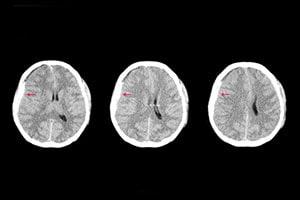

Hazards in the walkways can lead to people slipping or tripping and falling. While we often think of these accidents as causing minor cuts, scrapes, bruises, and broken bones, they can result in more serious injuries if the victim is hit in the head. People who are unable to catch themselves when falling may hit their head on the ground or another object. This can cause traumatic brain injuries to unsuspecting pedestrians. If you have been injured in an accident by a blow to the head, you should seek legal representation to recover medical bills and lost wages. For a free evaluation of your case, contact the Coral Gables brain injury lawyers at Wolfson & Leon at (305) 285-1115.

Trauma to the head is a common injury that can occur in a slip or trip and fall accident. Also known as the cranial bone, the area of the skull that surrounds the brain in made up of eight bones. When a person experiences a significant blow to the head, it can result in a fracture of the skull. When a part of the skull is fractured, you brain may be prone to receive more damage in an accident.

Injuries to the skull may also be characterized by how the fracture occurs. Fractures that occur in a straight line are considered linear, whereas multiple skull fractures are often referred to as comminuted.